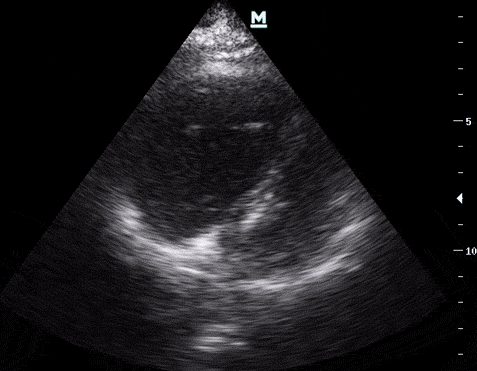

1- Kardiyak

APE’de EKO bulguları sağ boşluklara göre şekillenir;

Sağ ventrikül dilatasyonu (diyastol sonu sağ ventrikül oranı/sol ventrikül oranı > 1:1) ve D bulgusu.

Sağ ventrikül dilatasyonunun sıklıkla bulunduğu 3 önemli durum;

- Pulmoner emboli,

- Obstrüktif akciğer hastalığı,

- Sağ ventrikül enfarktı.

Sağ ventrikül disfonksiyonu (sağ ventrikül hipokinezisi, paradoksal septal duvar hareketi, McConnell bulgusu);

Paradoksal septal hereket, septumun sol ventriküle doğru yer değiştirmesi; McConnell ise, sağ ventrikül serbest duvarınının hipo/akinetik iken, apexin hiperkinetik olması olarak tanınır.